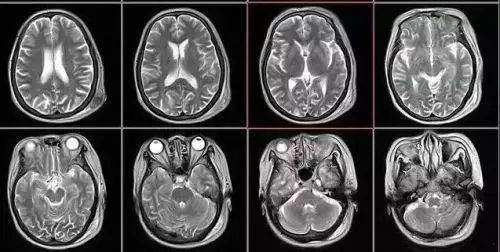

磁共振成像(MRI):摇一摇再看

核磁共振机使用较强大的磁场,使人体中所有水分子磁场的磁力线方向一致,这时磁共振机的磁场突然消失,身体中水分子的磁力线方向,突然恢复到原来随意排列的状态。简单说就相当于用手摇一摇,让水分子振动起来,再平静下来,感受一下里面的振动。根据信号差异,区分不同组织,包括肿瘤组织与正常组织,MRI已应用于全身各系统的成像诊断。效果最佳的是颅脑,及其脊髓、心脏大血管、关节骨骼、软组织及盆腔等。

(2)软组织和解剖结构显示清晰,对中枢神经系统、膀胱、直肠、子宫、阴道、关节、肌肉等检查优于CT

2、颈椎腰椎——最佳选核磁、次选CT

颈椎病、腰椎间盘突出等椎间盘疾病需要观察椎间盘与相应的神经根,要想更好观察这些软组织,最优选择就是核磁。同样,对于关节、肌肉、脂肪组织检查,核磁也是首选。